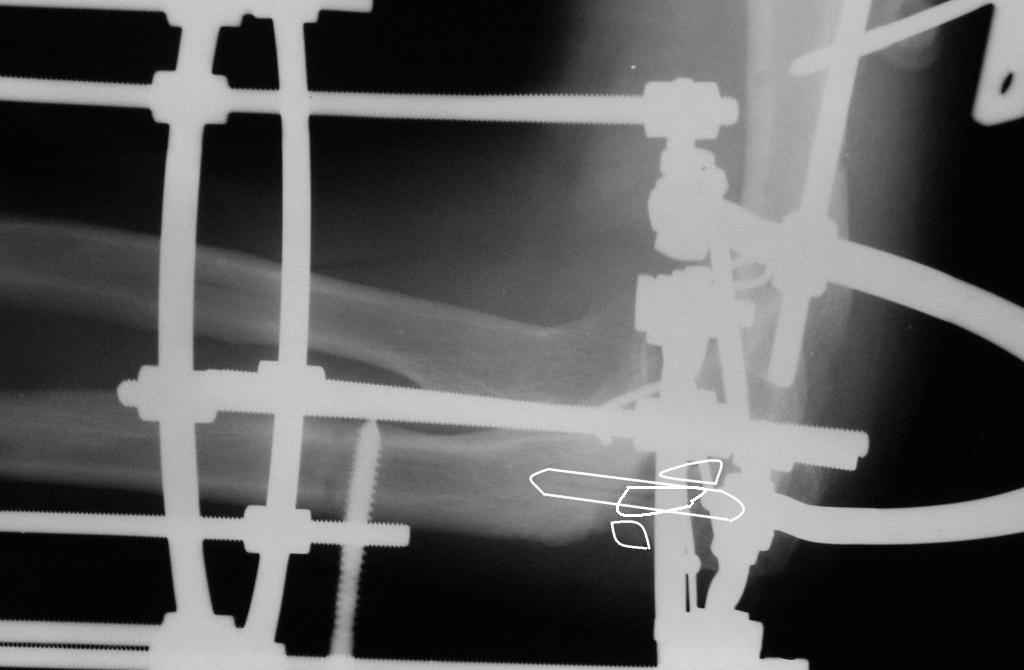

Коллеги! Сделана операция. Убрана рубцовая ткань, освежены концы до "кровяной росы", произведен релиз локтевого отростка и заднего отдела сустава - прошел до венечного отростка. После адаптации отломков выяснилось, что полное сопоставление происходит только на 1/4 периметра. Уложены аутотрансплантаты взятые из крыла подвздошной кости. Приведена схема. Через локтевой отросток проведены две спицы с упорными площадками с разбросом в 1 см, закрепленные на отдельном полукольце. Дана компрессия. Пятые сутки, рана заживает первичным натяжением. Выписываю. На 14 сутки буду пробовать движения.

Николай.